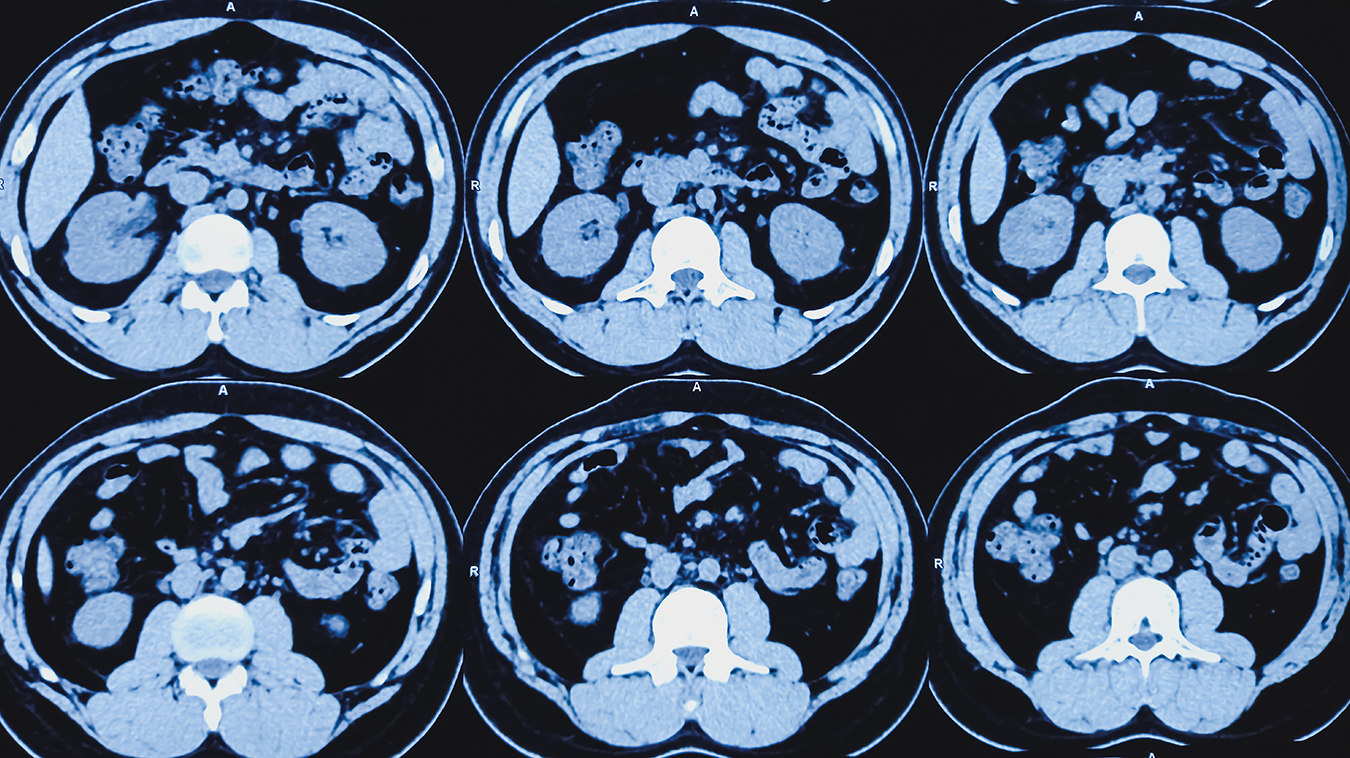

Computed tomography scans are often referred to as CT or CAT scans. It’s a type of medical imaging that uses ionizing electromagnetic radiation in the form of X-ray photons (energy) to create images of your body.

During a CT scan, a rotating X-ray source emits a narrow beam of photons through the body part of interest which is then recorded by an advanced detector on the other side. This results in a volumetric dataset that the computer reconstructs into numerous cross-sectional images, called tomographic images or slices. This creates three-dimensional (3D) images that can be viewed from multiple directions.

CT scans are very good at imaging bone but can also provide detailed information about soft tissues in the chest, abdomen, and pelvis, in addition to blood vessels. A CT may be preferred to evaluate fractures or look for cancers or blood clots.